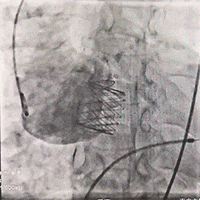

释放J-Valve瓣膜:

复查根部造影,未见明显反流,瓣膜形态和位置满意,双侧冠脉显影良好: